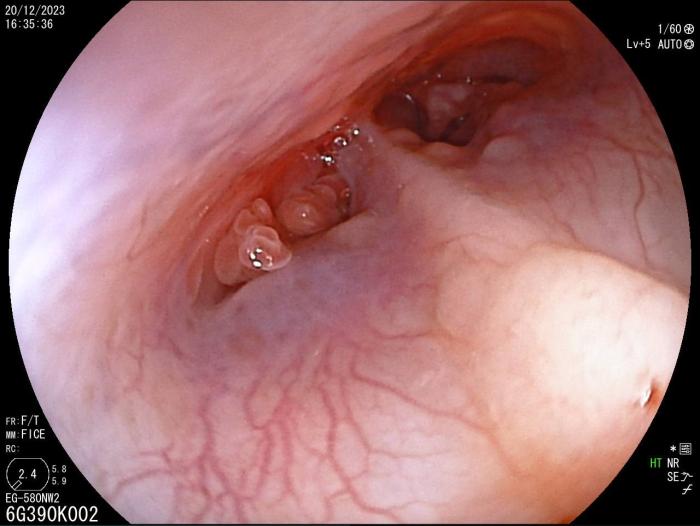

Rinoscopia anterógrada y retrógrada (día 6), con acceso a través de los ollares (acceso retrógrado) y a través de cavidad oral y nasofaringe (acceso anterógrado) con obtención de moco profundo para su cultivo bacteriano, sin observarse anomalías morfológicas (Figura 2), y otoscopia con miringotomía para el drenaje de contenido purulento y toma de muestra para cultivo bacteriano. Las muestras se envían al laboratorio de referencia.